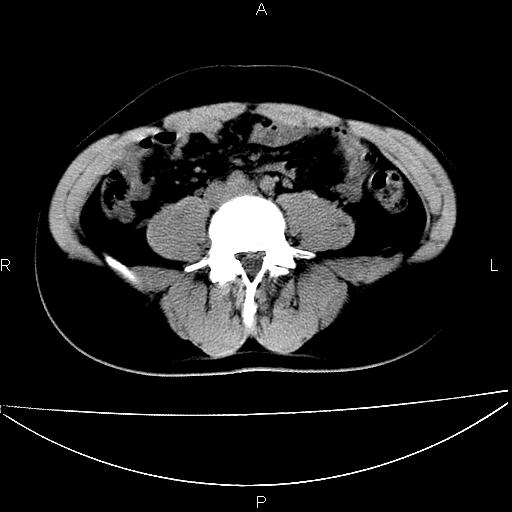

男 25岁 自述 尿频尿急,排尿困难20多天.无腰痛, b超说左肾盂轻度积水,左输尿管上端扩张.未见结石影. ct我看双侧肾盂轻度积水,双输尿管上端都扩张,大家看看能看见结石吗?

考虑肾外肾盂 前列腺轻度肿大 密度欠均 考虑炎性改变

箭头所指不是输尿管,壶腹型肾盂。

肾外肾盂,必要时+c